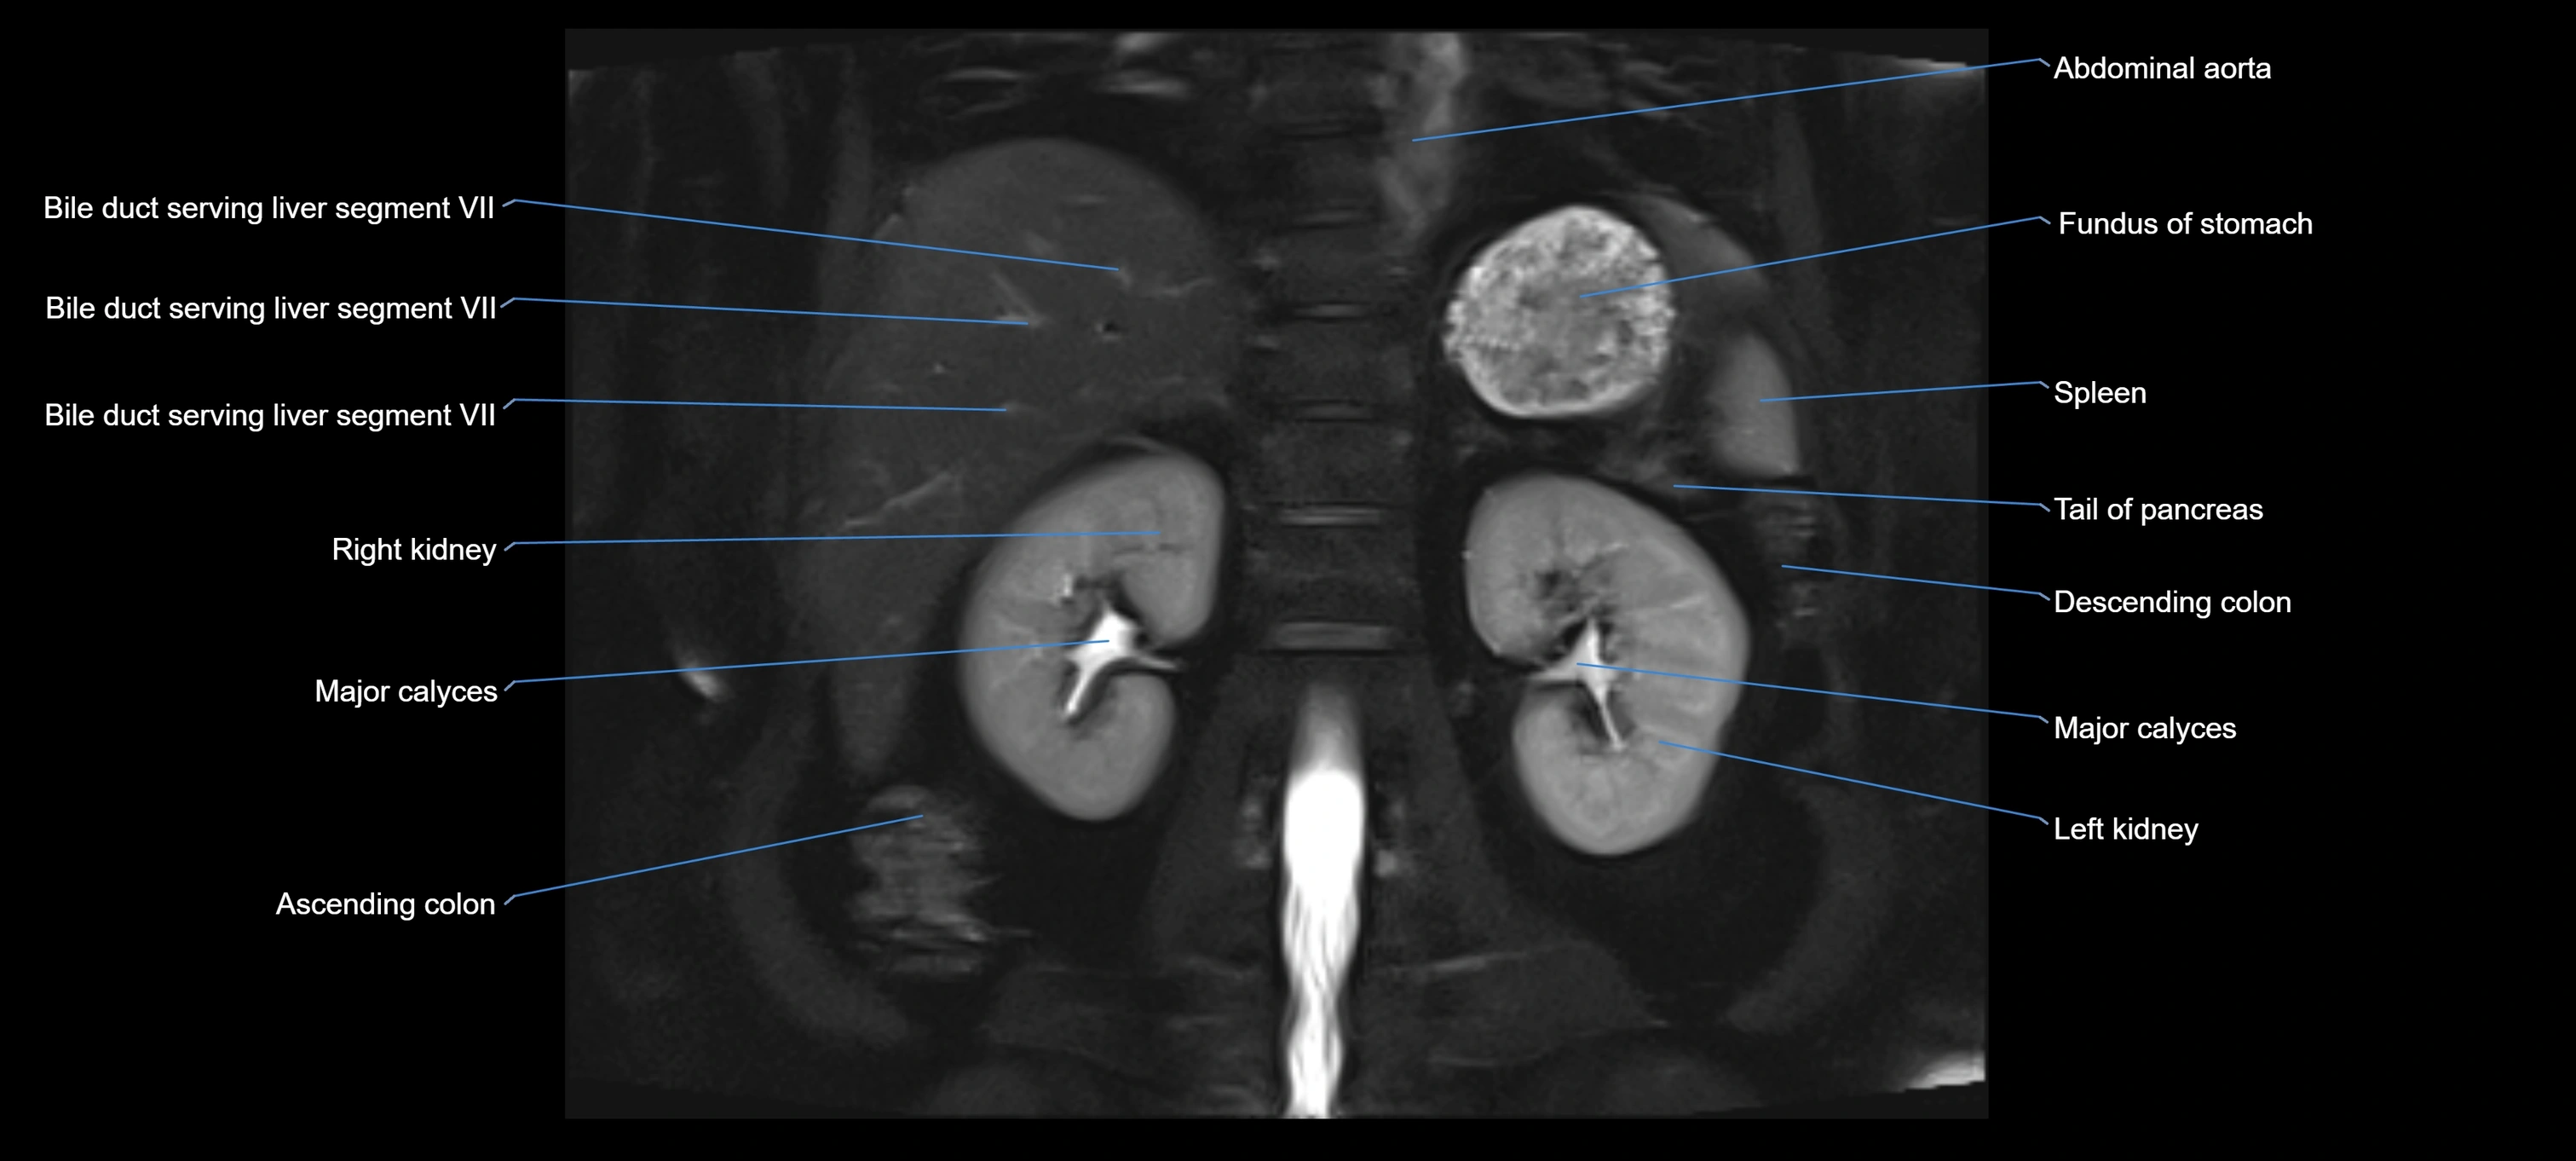

MRI image

image